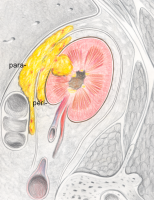

Als klinisch wichtige Komplikation der Pyelonephritis ist der Nierenabszess zu nennen. Die Abbildung zeigt im Schema die Abszedierung in und um die Niere (Abbildung 4)

Die Pathogenese der Abszessbildung in der Niere und weitergehend in der Ausbreitung der pyogenen Infektion in den peri- bzw. paranephritischen Raum sind in der Abbildung dargestellt (

Abbildung 5, s. auch Abbildung 4).

Ausgehend von einem Nierenabszess kann es zum Übertritt der pyogenen Infektion in den peri- bzw. paranephritischen Raum kommen. Die Pathogenese des peri- bzw. paranephritischen Abszesses zeigen die Abbildungen (

Abbildung 5, s. auch Abbildung 4). Ein wichtiges, erstes Diagnostikmittel ist neben den entsprechenden Laboruntersuchungen bei der Ausbreitung der Abszedierung über die Niere hinaus die Sonographie.